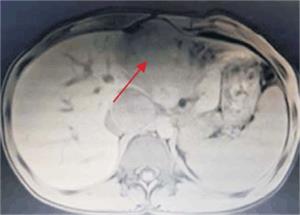

Tumoración que sustituye el lóbulo izquierdo con realce heterogéneo en la fase arterial que infiltra la vena suprahepática izquierda, contacta con la vena suprahepática media y la vena porta (figura 2) y (figura 3). Lesiones en los segmentos V y VIII. Extensas adenopatías en el hilio hepático. Nódulo peritoneal en fondo de saco de Douglas. Nódulo pulmonar derecho (figura 4).

Figura 3: Se observa tumoración que protruye a nivel de epigastrio, palpable al examen físico abdominal.